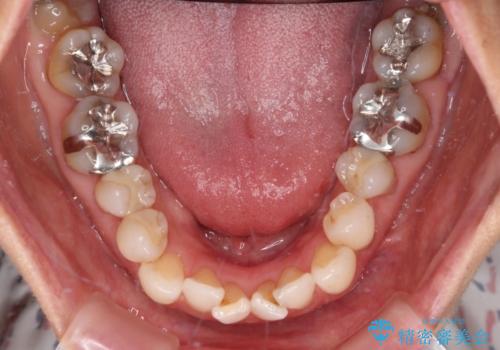

デコボコと銀歯 矯正治療とセラミック治療で綺麗な口元に

- 前歯のデコボコと口を開けたときに見える銀歯を気にして来院された患者様です。

矯正治療後に銀歯をセラミッククラウンなどに置き換えていくと、どうしても後戻りを起こしてしまうため、矯正治療が概ね終了した時点で銀歯を全てセラミックとし、最後に仕上げでインビザラインにを用いて細かいデコボコを改善していくこととしました。

とても明るい口元となり、人目を気にせず、大きく口を開けて笑えるようになりました。